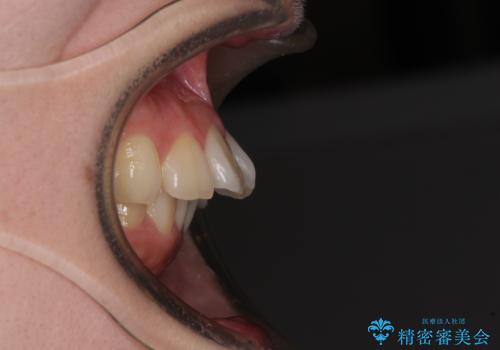

口元の突出感はないものの、上顎前歯が前方に傾斜して突出しており、前後に大きなズレがあり非常に深い咬み合わせとなっていました。

前突間を改善するため、上顎左右の第一小臼歯を抜歯してワイヤー装置にて矯正治療を行うこととしました。

深い咬み合わせは上顎前歯を引っ込ませる大きな障害となるため、咬み合わせの改善が非常に重要となります。やや期間はかかりましたが、当初狙った通りの仕上がりで治療を終えることができました。